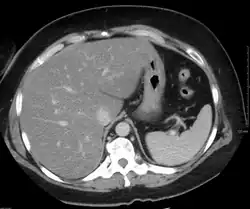

Liver steatosis (fatty liver disease) as seen on CT

Imaging studies are often obtained during the evaluation process. Ultrasonography reveals a "bright" liver with increased echogenicity. Pocket-sized ultrasound devices might be used as point-of-care screening tools to diagnose liver steatosis.[31] Medical imaging can aid in diagnosis of fatty liver; fatty livers have lower density than spleens on computed tomography (CT), and fat appears bright in T1-weighted magnetic resonance images (MRIs).

Histological diagnosis by liver biopsy is the most accurate measure of fibrosis and liver fat progression as of 2018.[9] Conventional imaging methods, such as ultrasound, CT and MRI, are not specific enough to detect fatty liver disease unless fat occupies at least 30% of the liver volume.[32]